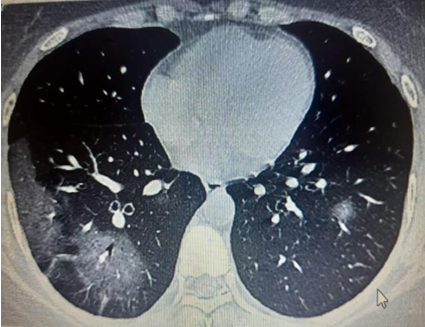

Fig. 4: Consolidation

Present study out of 107 cases 106 cases had abnormal HRCT findings out of which 99(92.5%) had bilateral abnormality and 7(6.5%) had unilateral abnormality and 7 had normal HRCT finding. Similar finding observed in [9] showed out of total of 175 chest CT scans were scored in this study. A total of 140 (80%) chest CT scans demonstrated bilateral infiltrates, and 31 (18%) chest CT scans showed unilateral infiltrates, whereas 4 (2%) chest CT scans had no abnormal findings. In our study, according to HRCT findings, GGO was seen in 70(65.4%) cases, consolidation in 34(31.8%), atelectatic band in 1(0.9%), crazy paving in 5(4.7%) cases, reticulation in 11(10.3%) cases, Peripheral hyperdensity in 9(8.4%), mediastinal LN and lymphadenopathy 2(1.9%) cases respectively, 1(0.9%) case with COPD, ground glass haziness, emphysematous changes, mild Fibrosis and septal thickening respectively. Similar findings observed in Sudhir Bhandari et al.119. (2020) showed that in an early phase of disease (10 d), among radiologically positive patients (8 out of 15) 12.50% patients had GGO, 75.00% patients had both GGO and consolidation, while remaining 12.50% patients had only consolidation in imaging of HRCT chest.